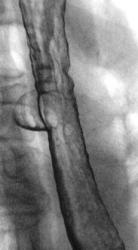

А это тоже дивертикул????

Изображение

Это тоже дивертикул???

или это два дивертикула, которые наложились друг - на друга?